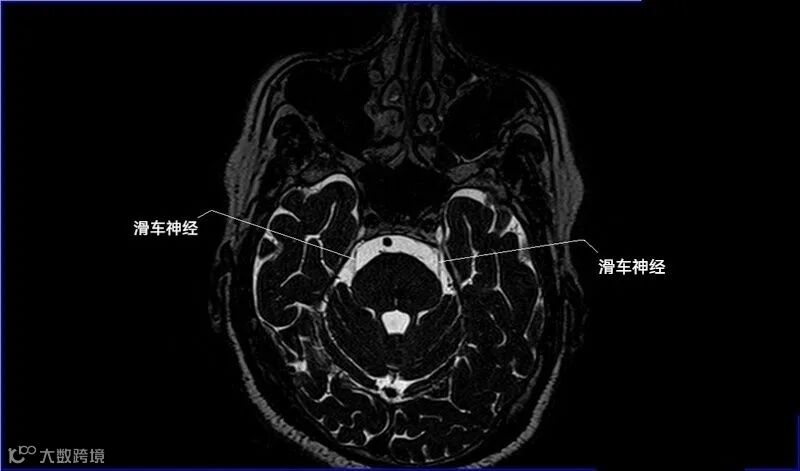

一嗅二视三动眼,四滑五叉六外展,

七面八听九舌咽,迷走及副舌下全。